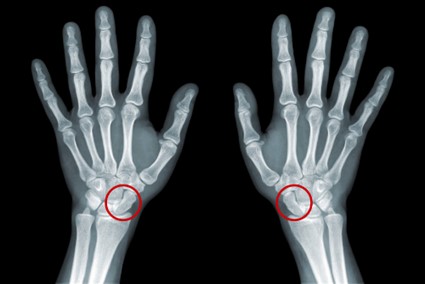

- Exames de Imagem: Ressonância magnética e radiografias para avaliar a extensão da lesão e a saúde das estruturas circundantes do joelho.